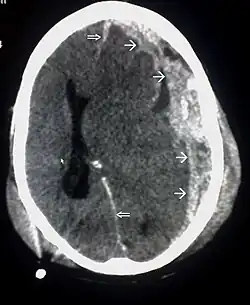

CT-scan waarop een hersenkneuzing, hersenbloeding, subduraal hematoom en schedelfracturen te zien zijn.[1] | ||||

Wanneer bloed zich ophoopt in of rond het brein, spreekt men van een hematoom.[4] Bij een intracerebraal hematoom vindt de bloeding in het hersenweefsel plaats (intra-axiaal). Voorbeelden van bloedingen buiten het hersenweefsel (extra-axiaal) zijn epiduraal hematoom, subduraal hematoom, subarachnoïdale bloeding en intraventriculaire bloeding.[27] Bij een epiduraal hematoom ontstaat er een bloeding tussen de schedel en het harde hersenvlies, de buitenste van de drie hersenvliezen.[4] Bij een subduraal hematoom ontstaat de bloeding tussen het harde hersenvlies en het spinnenwebvlies.[14] Een subarachnoïdale bloeding vindt plaats tussen het spinnenwebvlies en het zachte hersenvlies.[14] Wanneer er een bloeding ontstaat in het ventrikelstelsel, spreekt men van een intraventriculaire bloeding.[27]